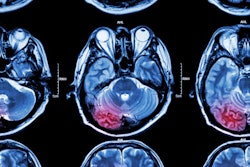

Advances in brain imaging technology may help identify more patients who are eligible for stroke treatment. Image courtesy of Dr. Gregory Albers.An ischemic stroke occurs when a cerebral blood vessel becomes blocked, cutting off the delivery of oxygen and nutrients to brain tissue. Clinicians have long thought that the area surrounding the core has the potential to be saved based on how quickly the blood flow can be restored. But over the past 20 years, researchers have been investigating whether brain imaging could detect patients with tissue that can still be salvaged by removing the blockage.

Albers and colleagues used automated software (Rapid, iSchemaView) to analyze perfusion MRI or CT scans to identify patients thought to have salvageable tissue. Study participants were randomized to receive endovascular thrombectomy -- the physical removal of the blockage -- plus standard medical therapy or medical therapy alone. Endovascular thrombectomy is currently indicated for use up to six hours following the onset of stroke.